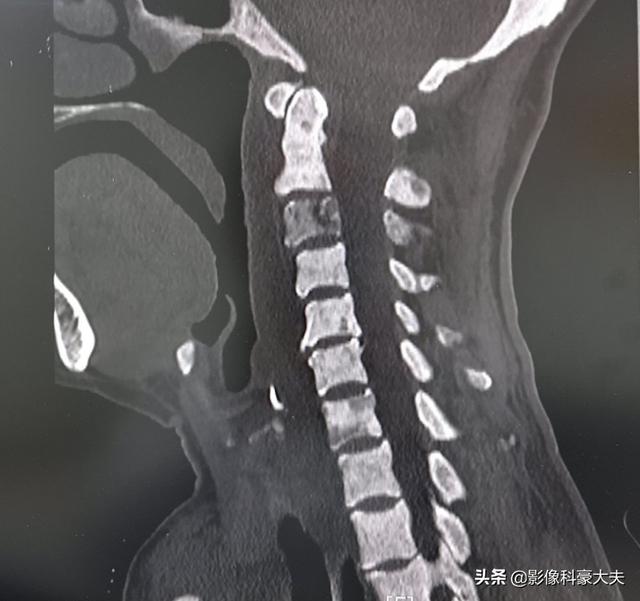

この老人は胃がんの患者で、手術前に首が少し痛いと言っていたが、その結果、頸椎CTで頸椎に広範な転移が見つかり、手術には適さなくなった。